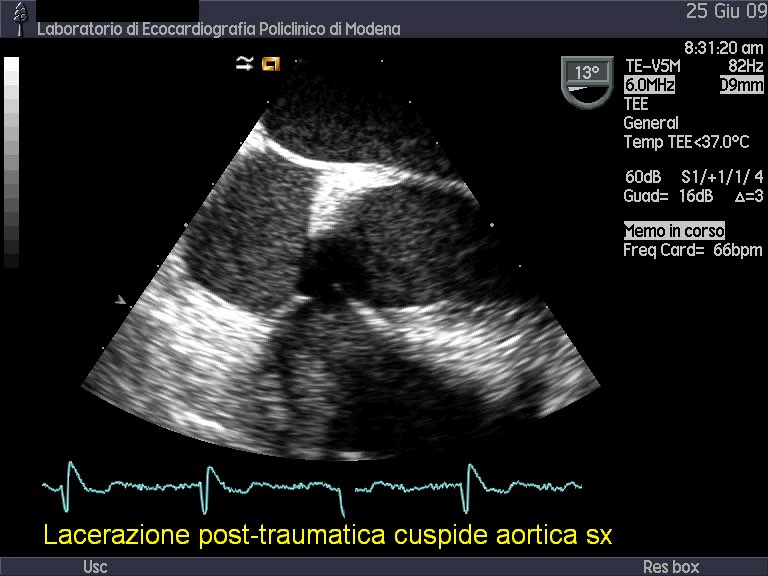

Titolo:

Insufficienza valvolare aortica acuta post-traumatica

Autore:

Andrea Barbieri